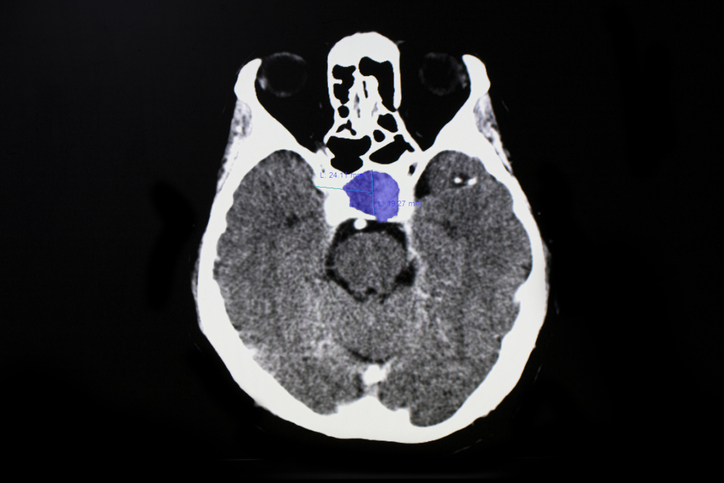

Αξονική τομογραφία εγκεφάλου ασθενούς με όγκο στην υπόφυση